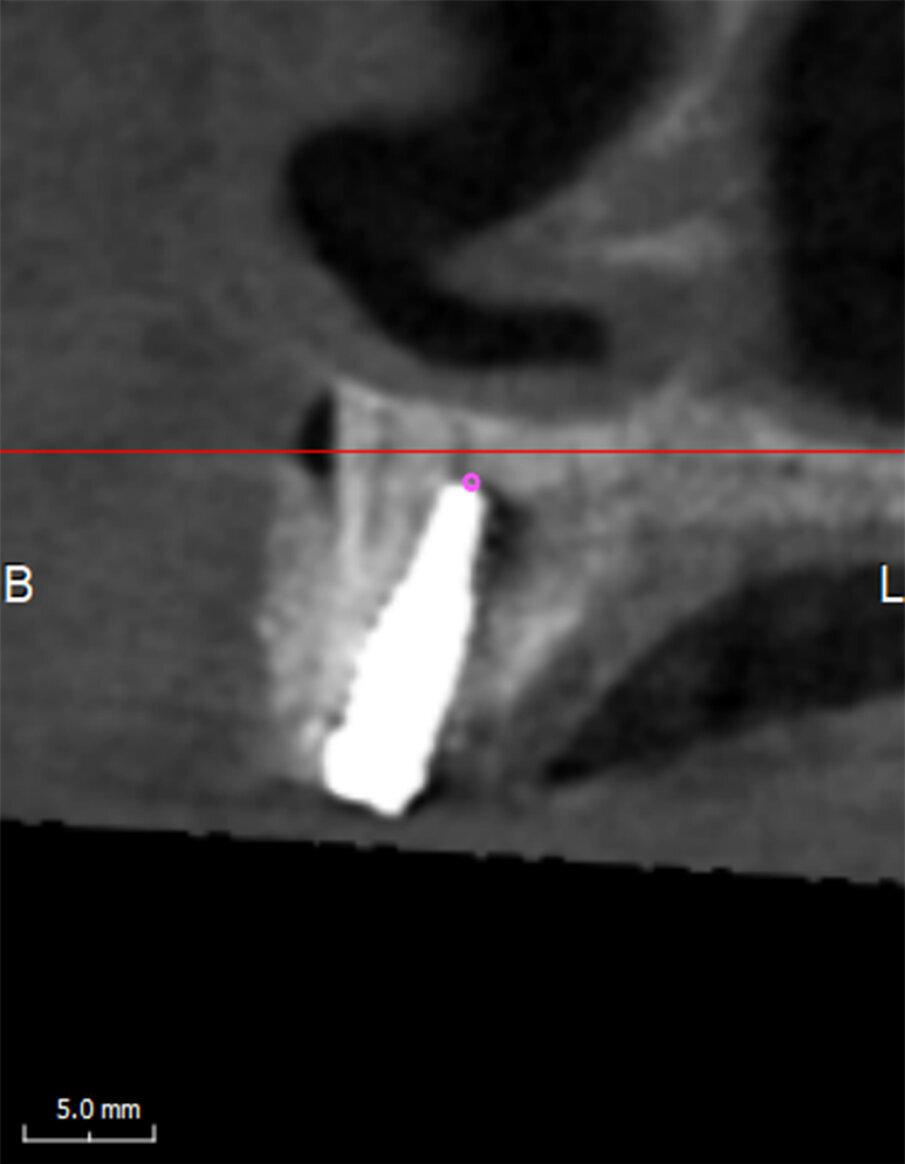

Una paziente di 62 anni, ASA 1 si rivolge alla nostra attenzione per richiedere una riabilitazione dell’arcata mascellare superiore essendo portatrice di protesi mobile totale. L’esame radiologico iniziale evidenzia una marcata atrofia ossea quindi viene progettato l’inserimento di 8 impianti dopo elevazione bilaterale dei seni mascellari al fine di realizzare un a protesi tipo Toronto-Bridge. Trascorsi 8 mesi dai sinus lift e dopo aver accertato la totale guarigione dei siti innestati con una CBCT viene eseguito l’intervento implantare in anestesia locale, sotto profilassi antibiotica, con chiusura dei lembi per prima intenzione e senza eseguire procedure di carico immediato. La paziente viene quindi controllata regolarmente ed a distanza di 7 giorni manifesta una sintomatologia algica localizzata alla zona 1.1 che inizialmente appariva compatibile con il normale decorso post-operatorio. Successivamente a 15 giorni la situazione era nettamente peggiorata trasformandosi in dolore localizzato e persistente con acutizzazioni che la paziente descriveva come “scosse elettriche” o “stilettate”. A questo punto è stata eseguita una nuova analisi della CBCT postoperatoria (Fig. 5) al fine di indagare in maniera più approfondita tale zona, l’analisi delle immagini ha evidenziato la presenza di un CS destro compresso dall’apice dell’impianto in posizione 1.1 (Figg. 6, 7). Tale condizione veniva subito riconosciuta compatibile con la sintomatologia della paziente e si procedeva a rimuovere e sostituire la fixture con una di lunghezza inferiore che non interessasse il decorso del CS (Fig. 8). Veniva quindi prescritta una terapia farmacologica post-operatoria comprensiva di antibiotici, antinfiammatori ed integratori di complessi vitaminici B. La paziente è stata controllata giornalmente manifestando un graduale miglioramento fino a scomparsa della sintomatologia algica a 15 giorni.

Fig. 4 - Immagine parassiale di CBCT raffigurante il forame accessorio del CS.

Fig. 6 - Immagine parassiale raffigurante l’impianto in sede 1.1 che comprime il CS.

Nella moderna chirurgia odontoiatrica la CBCT ha assunto un ruolo predominante nella valutazione pre-operatoria delle riabilitazioni di pazienti parzialmente e totalmente edentuli fornendo immagini affidabili ad alta risoluzione di gran lunga superiori alle precedenti tecnologie bidimensionali. È quindi facilmente capibile come un’attenta valutazione delle immagini pre-operatorie sia necessaria al fine di individuare l’eventuale presenza di un CS: l’immagine migliore per evidenziare il CS è la ricostruzione Panorex (Fig. 5), ricavata dalle immagini assiali, oppure l’immagine coronale (Fig. 3). Qui infatti possiamo evidenziare l’origine del CS dal nervo infraorbitario, la doppia curva a livello dell’apertura piriforme ed il decorso coronale fino all’emergenza nel forame accessorio. Da un punto di vista radiologico tuttavia bisogna ricordare che tutte le ricostruzioni (specialmente quelle con panorex e cross-sections/parassiali) possono portare alla formazione di artefatti quindi il nostro sospetto diagnostico andrà verificato sulle immagini assiali originali ripartendo dal forame infraorbitario e seguendo il percorso fino all’emergenza palatina (se radiologicamente evidente). Gli aspetti chiave da ricercare nelle immagini assiali sono la radiotrasparenza del contenuto del CS circondata da un orletto radiopaco come tipico di un canale infraosseo contenente un fascio vascolo-nervoso.